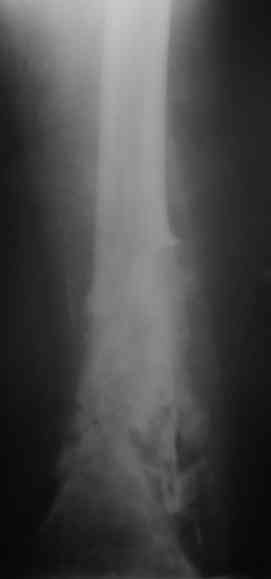

Уважаемые коллеги! Пациент лечился по поводу перелома н/3 бедра 1 год назад.

В настоящий момент: Несросшийся перелом н/3 правого бедра. Остеомиелит, свишевая форма.Контрактура коленного сустава.

Не факт, что поможет. Вариант классический в стране ГА Илизарова - санация - удаление всего мертвого с резекцией и потерей длины - аппарат для сращения и восстановления длины в один или два этапа (судя по ситуации). Многократно опробован. Тем паче, что остеомиелит хоть и травматический (операционный), но не канальный-тотальный (от штифта), а достаточно локален (от пластины).

Привет. Я имел в виду предложенную Вами программу лечения. Поражение кости остеомиелитическим процессом (судя по рентгенограммам) не канальное - когда спейсер можно поставить в канал после санации на какое-то время, а по всей окружности кости - когда придется делать спейсер в виде простой "болванки на арматуре). Вероятнее всего при хорошей санации получится дефект и укорочение. При втором этапе (как я понял, вы планируете БИОС) не факт, что восстановите длину и не "полыхнет" инфекция. Поэтому и предложена другая программа. Ваше право выбора - удачи на сложном пути избавления больного от ятрогенного о\миелита. Если проинформируете, что получилось, спасибо.